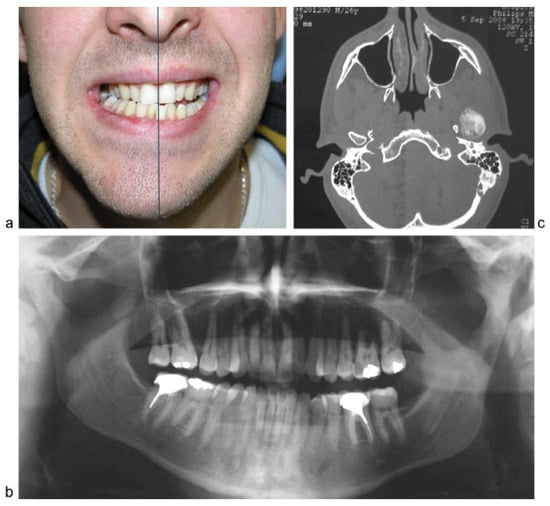

Condylar Osteochondroma Treated with Total Condylectomy and Preservation of the Articular Disc: A Case Report

Case Report